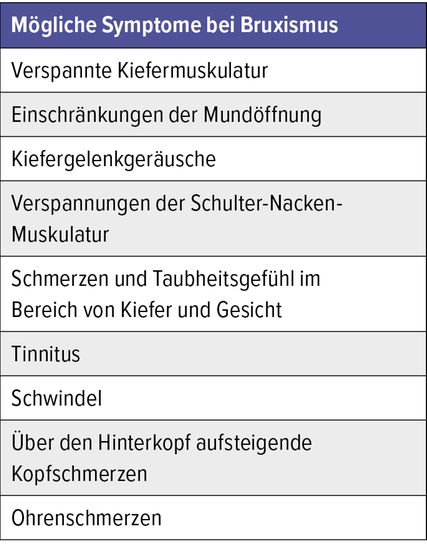

Symptome

Bruxismus ist ein Frühsymptom einer Dysfunktion des kraniomandibulären Systems. Der Begriff «System» soll unterstreichen, dass es sich um eine Störung handelt, die den Kauapparat im komplexen Zusammenwirken mit seinem umgebenden System, dem Muskel-Faszien-Apparat, den Kopfgelenken und der Halswirbelsäule betrifft. Daher sind auch die Symptome vielschichtig. Die häufigsten Symptome sind Kopfschmerzen, Kiefergelenkgeräusche, Einschränkungen der Mundöffnung, zudem Verspannungen der Schulter-Nacken-Muskulatur und Schmerzen im Bereich von Kiefer und Gesicht, Tinnitus und Schwindel (Tab. 2).

Alle diese Beschwerden werden häufig in der Allgemeinarztpraxis genannt und können die verschiedensten Ursachen haben. Vorliegender Artikel soll für die Beachtung des Zusammenhangs der genannten Symptome aus Tabelle 2 mit Funktionsstörungen im Bereich des Kiefergelenks sensibilisieren. Hinweisgebend ist die Klage der Patient:innen über eine verspannte Kaumuskulatur nach dem morgendlichen Erwachen, manchmal auch Ohrenschmerzen. Die Patient:innen streichen intuitiv die Kiefermuskulatur aus und beklagen auf Nachfrage Schmerzen und Verspannungen in diesem Bereich. Der M. masseter ist dann bei Palpation empfindlich. Manchmal ist ein Gelenkkrepitus bei Öffnung des Kiefergelenks zu hören oder die Mundöffnung ist vermindert. Die normale Mundöffnung beträgt 3 Querfingerbreiten in Längsrichtung (Abb. 1). Bei Ausschluss von Pathologien im HNO-Bereich sind diese Symptome verdächtig auf Kiefergelenkstörungen.3

Ein weitverbreitetes Symptom ist die Verspannung der Schulter-Nackenmuskulatur. Eine Studie von Simone Gouw et al. zeigte 2020 sowohl eine Kohärenz der Muskelkontraktion des M. masseter und M. sternocleidomastoideus als auch eine Kokontraktion von M. masseter und M. sternocleidomastoideus.4 Okzipital aufsteigende Kopfschmerzen werden ebenfalls häufig beklagt.